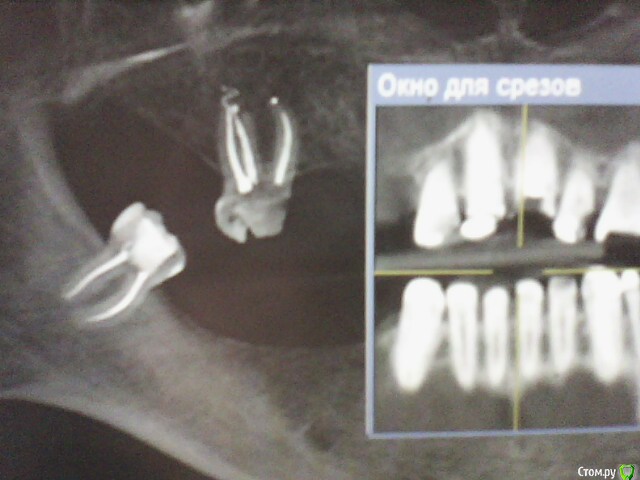

ОльгаS Опубликовано 16 декабря, 2014 Автор Поделиться Опубликовано 16 декабря, 2014 (изменено) Будет удален передний корень, где сломан штифт, и верхняя правая шестерка - под вопросом, но сама склоняюсь к тому, что бы ее сохранить, один их предложенных мне специалистом вариантов - 2 импланта, верхняя челюсть, и 4 - нижняя, в другой клинике предложили, удалить шестерку, тогда 3 импланта - верхняя, и 5 - нижняя, какой вариант все же более оптимален, мне самой, естественно, не определиться, да и как, если один специалист заявил, что слева в нижней челюсти близко расположен челюстно-лицевой нерв и имплант он там ставить не будет, а установит два и сделает один зуб подвесным, т.е. будет мостик, клиники обе - бизнес-класса. Изменено 16 декабря, 2014 пользователем ОльгаS Ссылка на комментарий

Doc Опубликовано 16 декабря, 2014 Поделиться Опубликовано 16 декабря, 2014 Проблема в том, что специалисты, к которым обратилась в реале имеют разное мнение:По этим двум скриншотам на форуме будет еще больше разных мнений. Нужны либо более качественные снимки, либо личная консультация у имплантолога и ортопеда вместе. Ссылка на комментарий